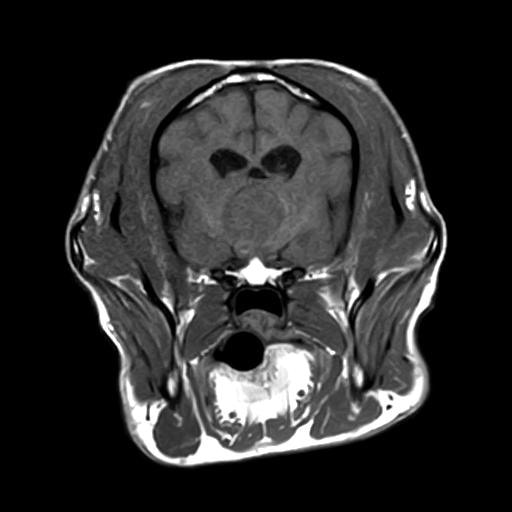

MRI画像:クッシング症候群の犬の下垂体腺腫

上記のような症状が認められた場合、まず血液検査・腹部X線検査などにより、除外診断を行います。臨床症状を含め、特徴的な所見が認められた場合、クッシング症候群の確定診断のためACTH負荷試験と呼ばれる検査を行います。状況により、エコー検査、CT/MRI検査を行い、コルチゾール分泌に関わる下垂体や副腎の状態を確認します。クッシング症候群と診断された場合は、お薬によるコントロール、原因によっては外科手術などが必要となってきます。